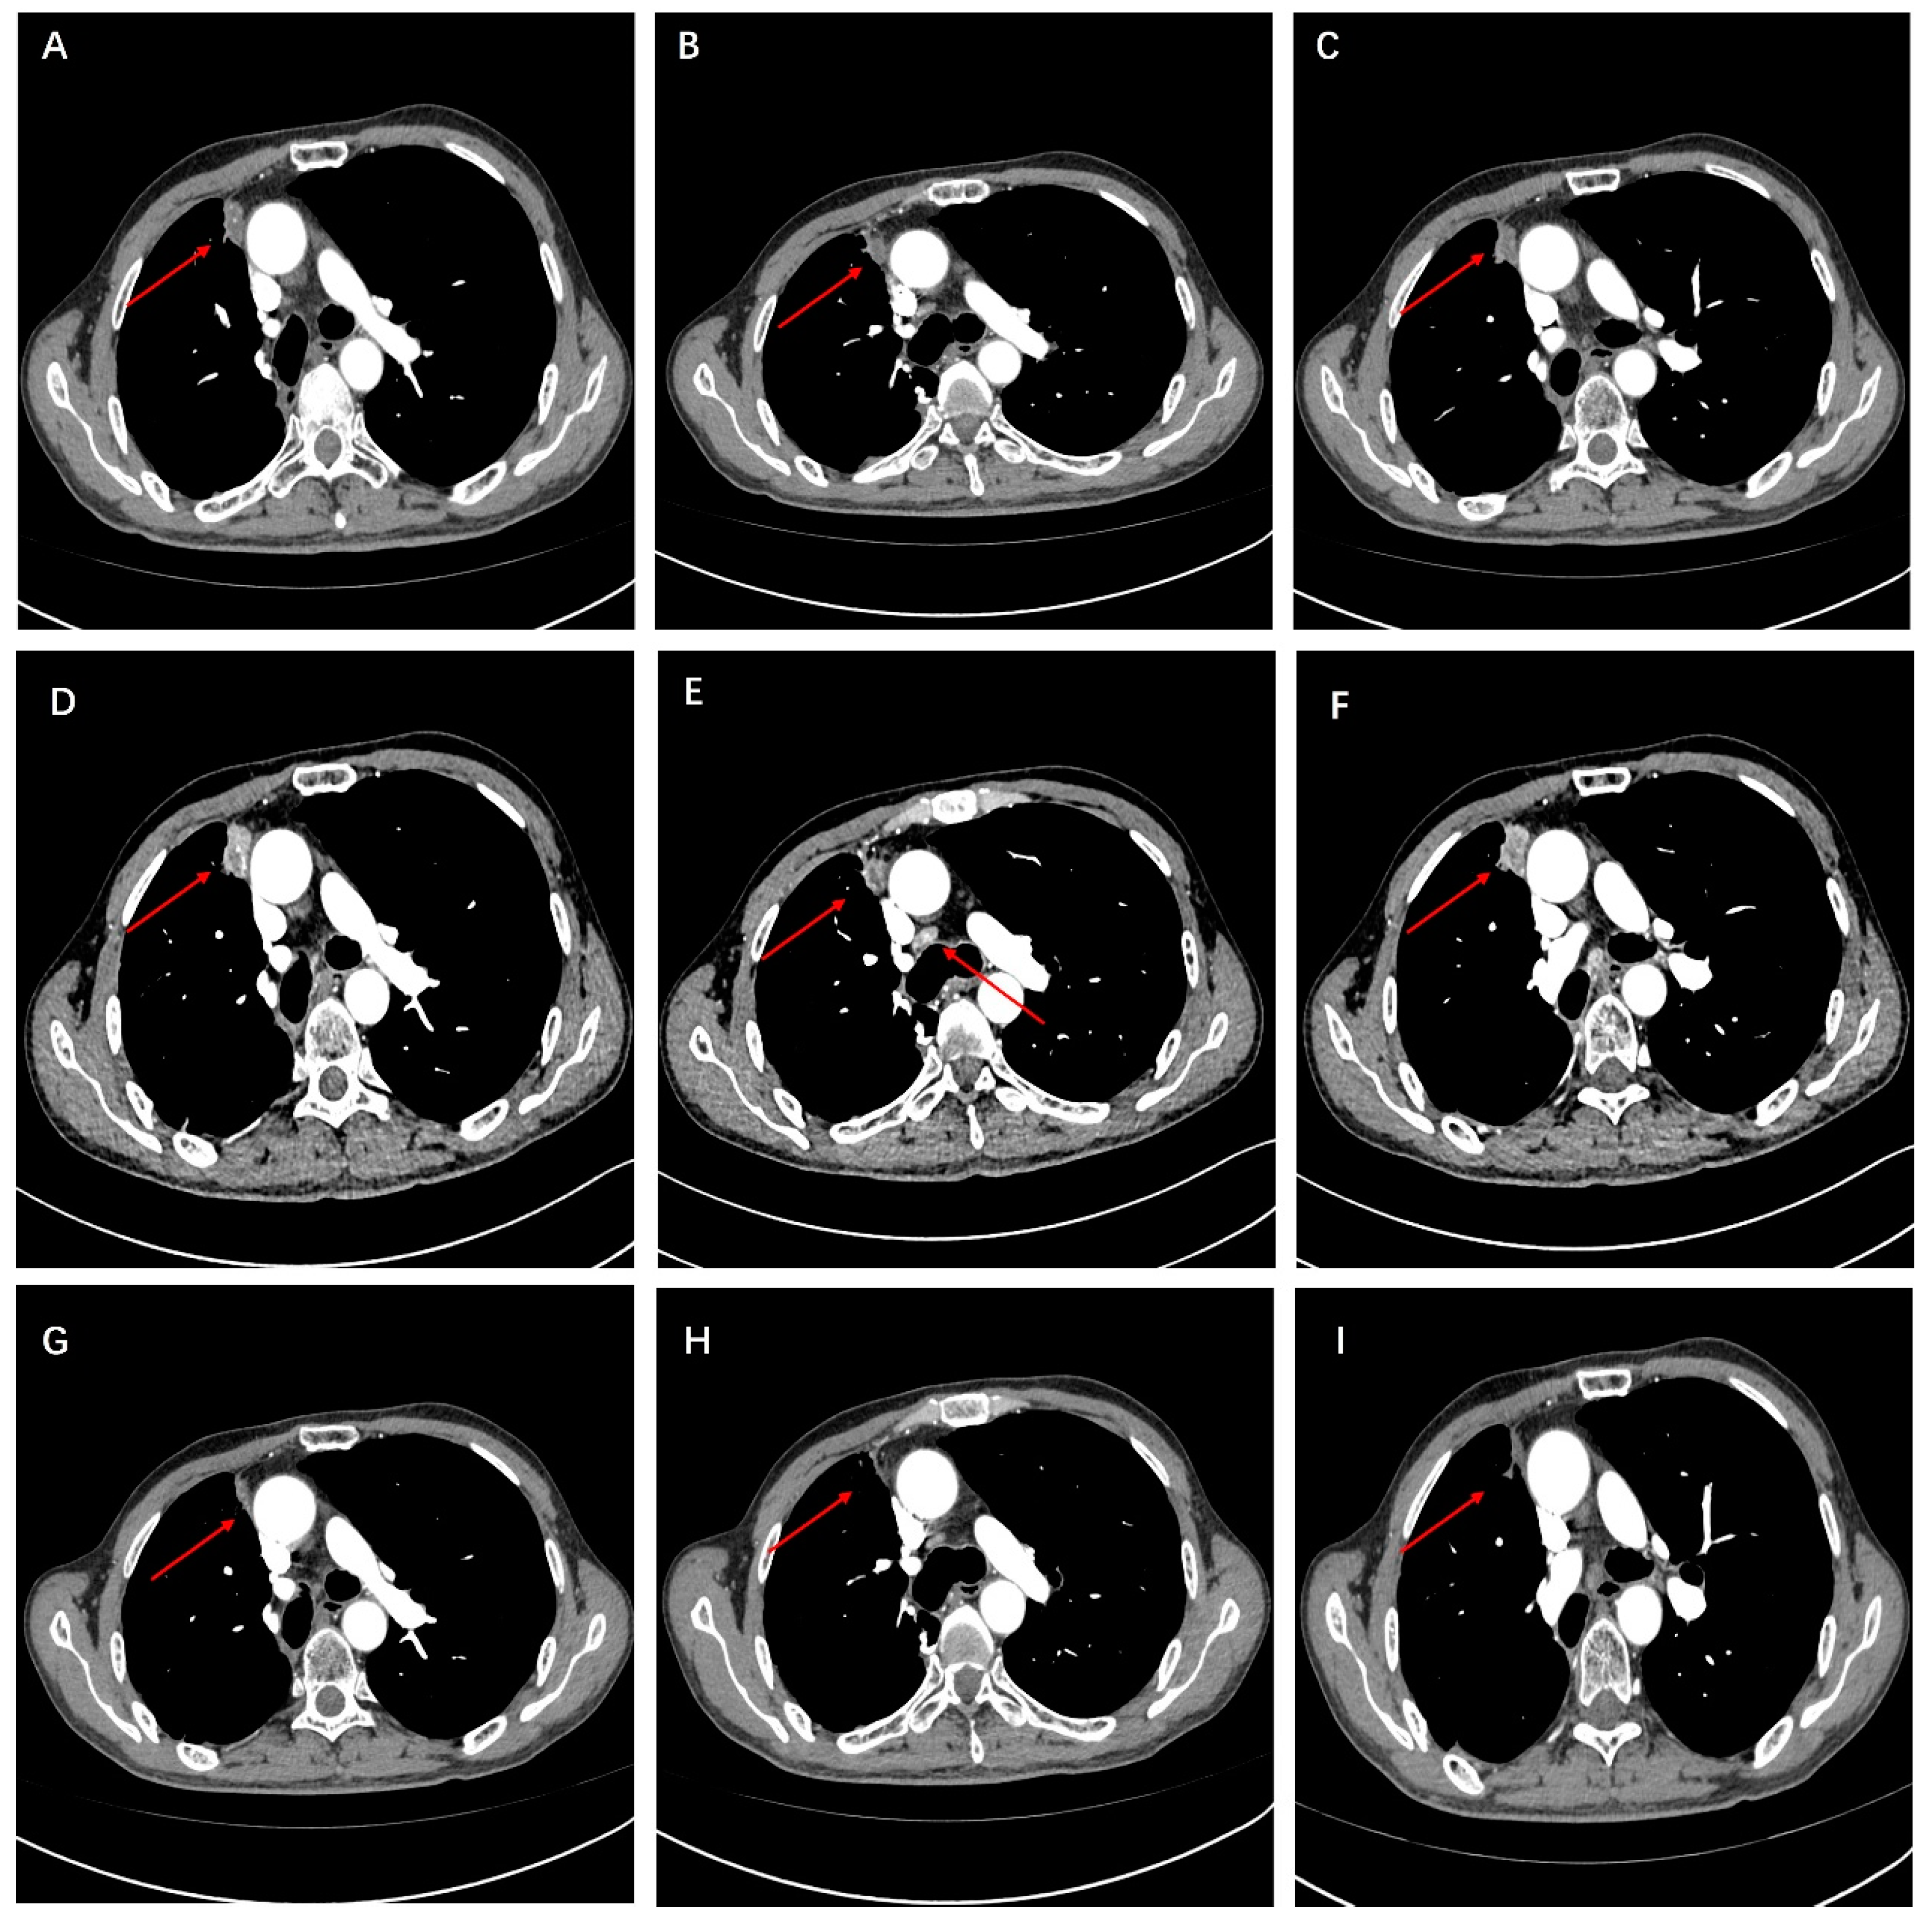

A 58-year-old Chinese male patient was admitted to the Sun Yat-sen University Cancer Center in March 2021, complaining of a persistent cough for two weeks, having smoked for 38 years. Chest computed tomography (CT) revealed a solid mass measuring 40 mm × 30 mm in the lower lobe of the right lung. Enlarged ipsilateral hilar and mediastinal lymph nodes were identified. There was a small amount of pleural effusion in the right chest cavity (Figure 1A–C). The pathology report from the CT-guided lung mass biopsy indicated NSCLC. The cytological examination of pleural effusion revealed no malignant tumor cells. There was no evidence of brain metastases radiographically based on a preoperative brain MRI, and a stage of cT2aN2M0 was determined. Following the completion of relevant preoperative evaluations, the patient underwent curative right lower lobectomy and mediastinal lymph node dissection on 9 March 2021. Pathological examination revealed metastasis to one hilar lymph node, one subcarinal lymph node, and one para-bronchial lymph node. The tumor tissue exhibited poorly differentiated infiltrating adenocarcinoma morphology with spread through airway space (STAS). The gross pathology examination indicated the tumor size was 45 mm × 38 mm × 35 mm, leading to an upgrade in staging to pT2b. According to the 8th edition of the AJCC (American Joint Committee on Cancer) staging system, the disease was diagnosed as stage IIIA adenocarcinoma of the lung (pT2bN2M0).

Figure 1.

(A–C) Preoperative CT of the chest revealed a space-occupying lesion in the lower lobe of the right lung.